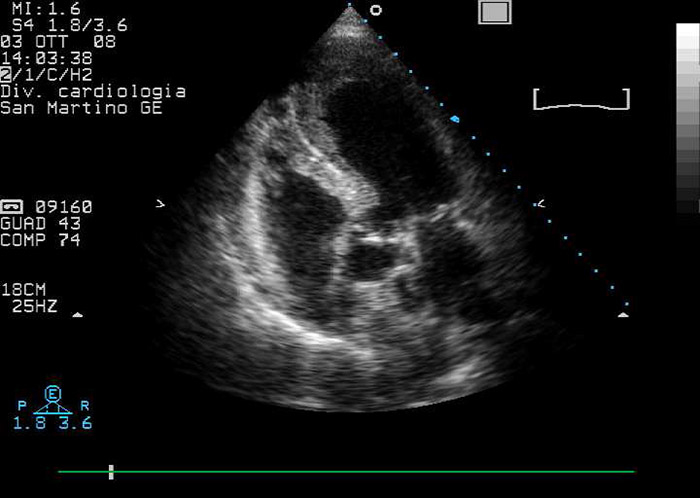

Figure 1

Echocardiographic modified four/five chambers view: note apical ballooning and apical mural stratified thrombus.

A routine electrocardiogram showed anterior-lead ST-segment elevation; transthoracic echocardiography (TTE) revealed apical ballooning, impaired LV ejection fraction (40%) and a stratified LVT (fig. 1). An ST elevation myocardial infarction (STEMI) complicated by acute leg ischaemia was then supposed. Recommended pharmacological treatment for STEMI was initiated [1]. Urgent coronary angiography and left ventriculography were performed, which showed normal epicardial coronary arteries and confirmed apical ballooning complicated by an apical LVT; STEMI was thus excluded and ABS was then postulated. Fogarty balloon thrombectomy was successfully executed to resolve the peripheral ischemia. Serum troponin I levels peaked at 1.09 µg/l.